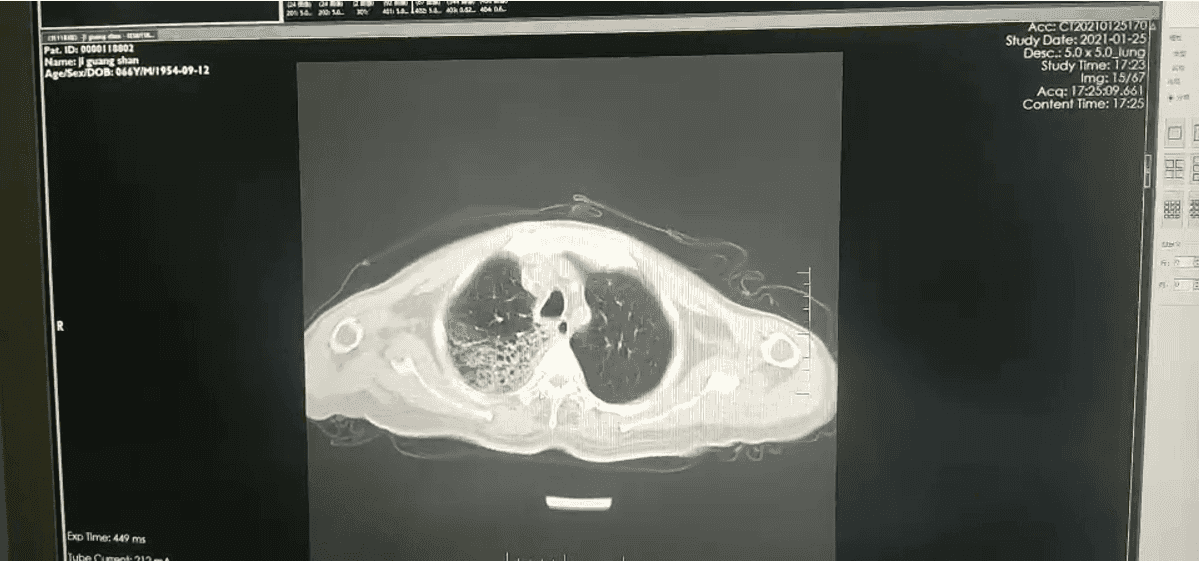

铁蛋白测定: 血清铁蛋白 1242ng/ml。转铁蛋白测定: 血清转铁蛋白 0.663 g/l。胸部 CT: 两肺间质性炎症。两侧少量胸腔积液(图 1)。

图 1:入院第一天胸部 CT,两肺间质性炎症两侧少量胸腔积液咽拭子培养: 未生长致病菌结核菌涂片(痰液): 抗酸染色:阴性细菌涂片(痰液): 革兰染色涂片见 G+球菌、G-球菌各少许血培养(双侧四瓶):。